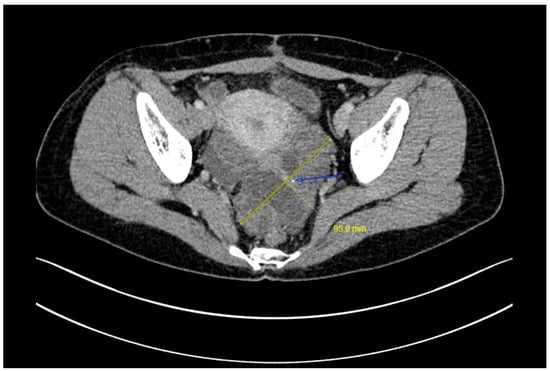

A right ovarian immature teratoma, grade 2, stage IC2 was diagnosed based on the FIGO stage classification for ovarian tumors. A chemotherapy regimen including bleomycin, etoposide, and cisplatin (BEP) was given for three cycles based on the NCCN clinical guidelines for ovarian germ cell tumors. AFP levels quickly decreased from 27.8 ng/mL to normal after two cycles of chemotherapy, and the last cycle was completed in mid-March 2022. The serum CA19-9 was less than 2 U/mL before surgery. Repeat ultrasonography conducted one month after the surgery did not show any abnormalities, but an ultrasound examination on five days after the last cycle of chemotherapy showed an approximately 8-cm solid cystic mass located in the left posterior uterus. The patient was then referred to our hospital. A repeat blood draw showed that serum AFP, CA125, NSE, and CA19-9 were all within normal ranges. Recurrence of immature teratoma and progressive disease could not be excluded. Further ultrasonography conducted by an expert demonstrated an 8.0 × 7.3 cm mixed-echo, lobulated mass with clear boundaries in the left adnexal area. The presence of lipid and hair-like echo, as well as a CDFI that revealed only scattered, short strips of blood flow signals in a small portion of the mass, were suggestive of GTS (Figure 2). Enhanced abdominal-pelvic CT was also used to determine the diagnosis and showed a comparable result to the ultrasound (i.e., a solid 8-cm cystic mass with undetermined malignancy), and no enlarged retroperitoneal lymph node was observed (Figure 3).

Figure 3. A 9.5 × 6.2 cm mass was noted left posterior of the uterus with an enhancement of solid component but not cystic component, no enlarged retroperitoneal lymph node was noted (arrow, calcification).